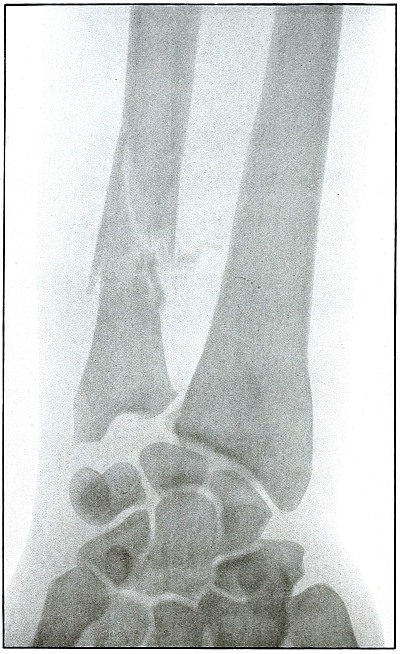

Plate 41.

[Pg 93]

Rifle—Plate 41.

UPPER EXTREMITY.

Gunshot Fracture of the Wrist.

Wound of entrance, posterior aspect of forearm over the lower end of

the radius, with the bullet ranging forward and slightly downward to

the wound of exit and covering with great laceration the anterior

aspect of the wrist joint.

The range was close, and the energy of the high velocity of the

missile was imparted to fragments, which, becoming “secondary

missiles,” emerged with the projectile to cause extensive laceration

and destruction of tissue.

The case was received for amputation in the second week, when a grave

degree of infection extended in a cellulitis to the elbow. The ulnar

nerve and vessels were intact, but the flexor tendons were almost

entirely destroyed.

The plate, made after several weeks, when infection was under control

and after the end of the radius and fragments of the carpus had been

informally removed, shows a rarefaction of the carpus and proximal

ends of the metacarpus, due to infection and disuse.

Frequent incisions and extension of drainage, with removal of detached

fragments, was continued for several months. The wound was closed in

the sixth month, with ankylosis and deformity of the wrist,

as shown in plate 42.